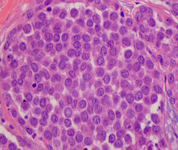

Histopathology of pleomorphic lobular carcinoma in situ (LCIS)

Courtesy of Dr Sunati Sahoo, University of Louisville; used with permission